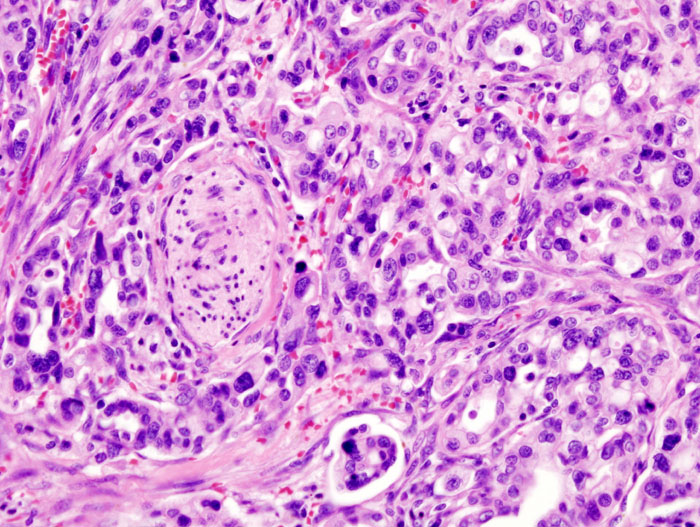

Il gruppo di ricerca ha così osservato che in ogni campione di tessuto sano di pancreas erano presenti diversi gruppi di cellule che sono a tutti gli effetti dei precursori di un tumore (PANcreatic Intraepithelial Neoplasia, PanIN, ma per semplicità li chiameremo precursori) a carico delle cellule duttali. In pratica, una descrizione dettagliata dal punto di vista morfologico degli istanti iniziali di quelli che potrebbero un giorno diventare degli adenocarcinomi duttali.

L'aspetto più sorprendente però è il numero di questi precursori: in 38 campioni sono stati trovati 889 precursori, con una media di 21 precursori per campione (e un range da 4 a 92). Qualche dato: la maggior parte di questi precursori aveva una dimensione inferiore a 0,5 cm, l'86% conteneva meno di 100.000 cellule, il 30% conteneva meno di 1000 cellule. Entità microscopiche.